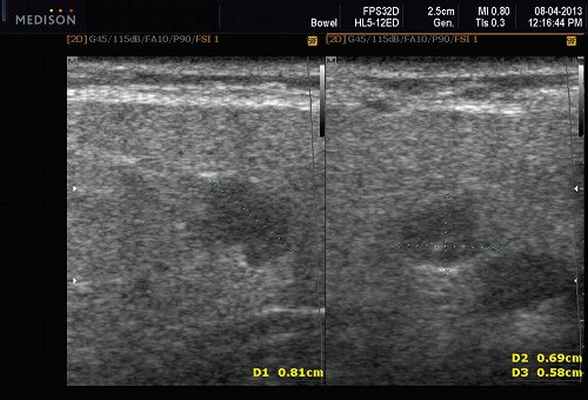

Рис. 5. Камень протока поднижнечелюстной слюнной железы.

Рис. 6. Камень в паренхиме поднижнечелюстной слюнной железы.

Рис. 7. Камень в протоке поднижнечелюстной слюнной железы.

- обструктивные сиаладениты, развивающиеся при затруднении оттока слюны при обструкции выводного протока камнем (рис. 5-7) или сгустившимся секретом, а также вследствие рубцового стеноза протока. По распространенности процесса различают очаговый, диффузный сиаладениты и сиалодохит - воспаление выводного протока. Течение процесса может быть острым и хроническим;